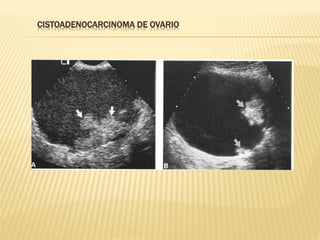

CISTOADENOCARCINOMA DE OVARIO

NEOPLASIA MALIGNA DEOVARIO  CARACTERISTICAS ECOGRAFICAS GENERALES  Masas sólidas o quística con componente sólido  Capsula con perdida de la continuidad  Frecuentemente bilaterales  Imágenes endo o exofiticas  Tabiques con vasularización  Flujo doppler con baja resistencia  Ascitis